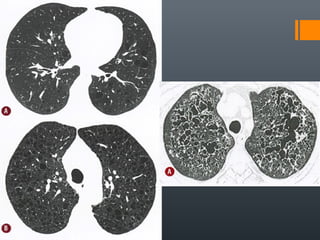

O documento discute vários conceitos radiológicos incluindo consolidação, atelectasia, nódulos, pseudocavidades e padrões intersticiais, fornecendo definições, sinais e diagnósticos diferenciais para cada tópico. Ele também discute a redução da atenuação pulmonar e fornece um link para mais informações.